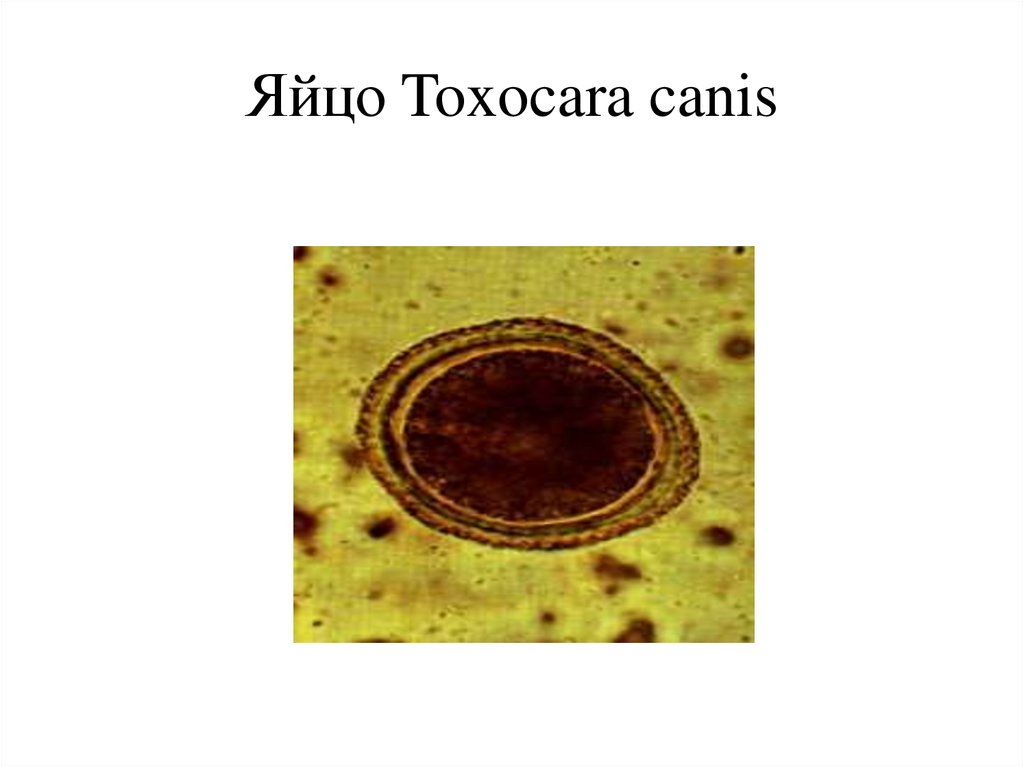

Микрофотографии яиц гельминтов Toxocara canis

Раздел: Фотоэссе